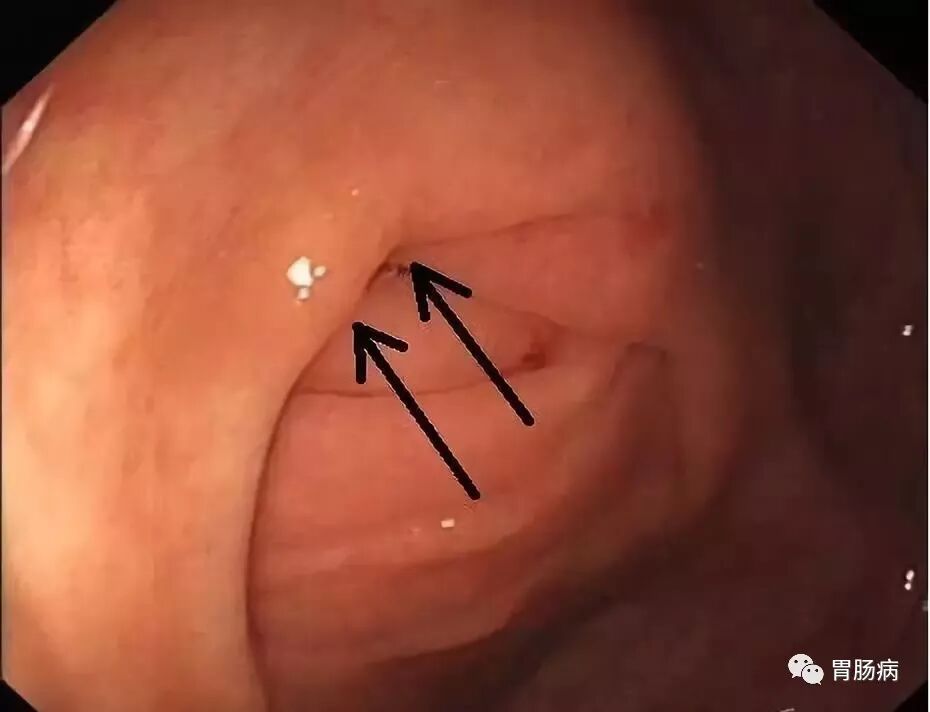

充分的肠道准备会有效减少ERAT操作时间,正常的阑尾开口部都被Gerlach’s瓣覆盖(如图,双箭头示Gerlach’s瓣);会造成插管困难,加上特制的锥形透明帽后插管就变得相对容易。

通过内镜前端的透明帽的帮助下,推开Gerlach’s瓣(黄箭头),并进行阑尾腔插管。